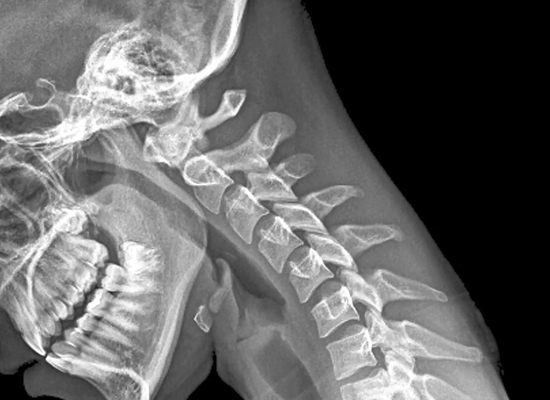

Contamos con equipos de rayos x digitalizados para la realización de cualquier estudio Radiologico como son:

• Radiografía de Cabeza y Cuello

• Radiografía de Tórax